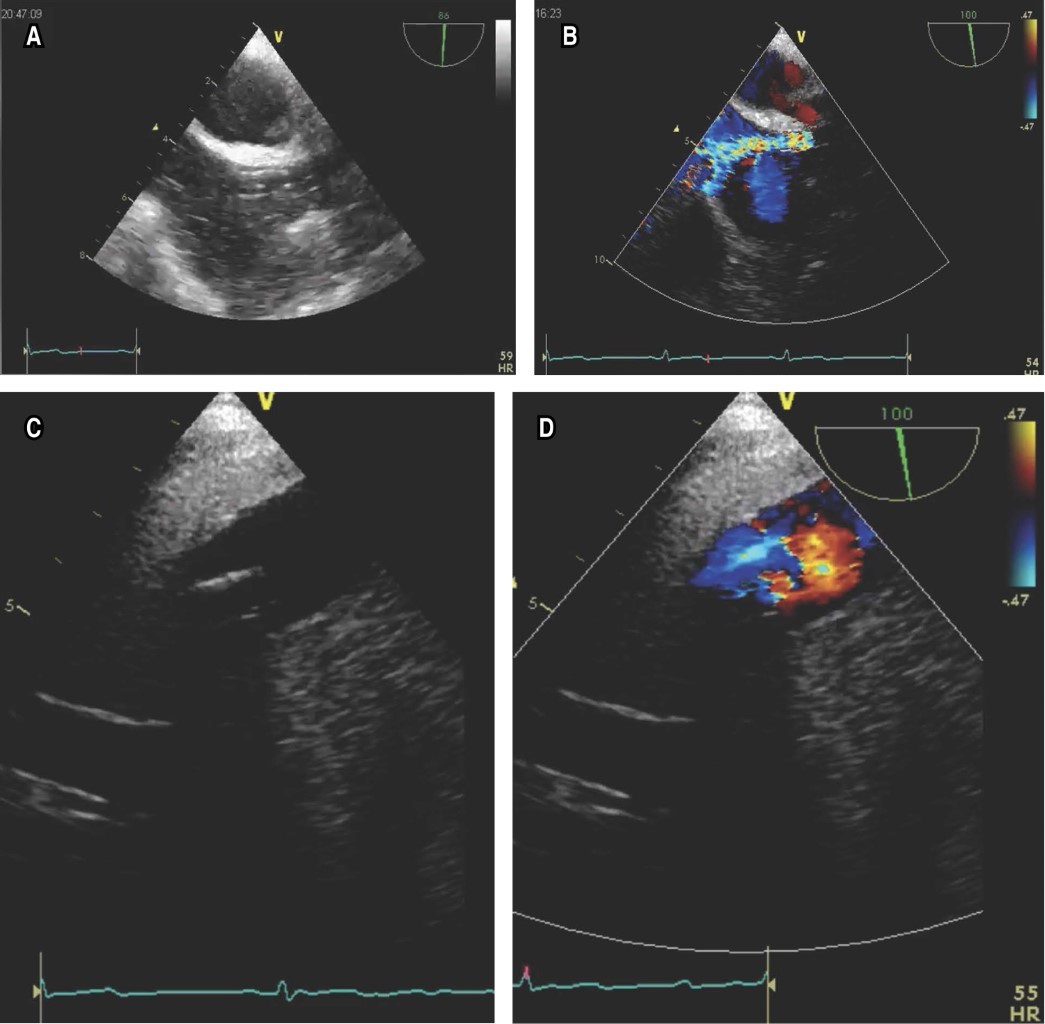

Como primer paso del flujograma (Figura 1), todo el personal debe tener una EPP adecuada y proteger la sonda del ETE (Figura 2A). Después de la sedación intravenosa, se inserta la sonda de ETE, siendo la proyección seleccionada para guiar el procedimiento la vista bicaval esofágica media de 90-110 grados (Figura 2B), donde podemos guiar en tiempo real el posicionamiento correcto de la cánula de retorno (yugular) (Figura 3A), que debe colocarse en la porción media de la aurícula derecha en dirección a la válvula tricúspide. El flujo adecuado puede evaluarse mediante Doppler color (Figura 3B). La sonda de ETE con el mismo grado de angulación se avanza distalmente hacia el esófago para observar la vena cava inferior y la cánula de extracción (femoral) que debe estar separada 8 a 10 cm de la cánula de retorno (Figura 3C y D); esto limita los fenómenos de succión y recirculación.